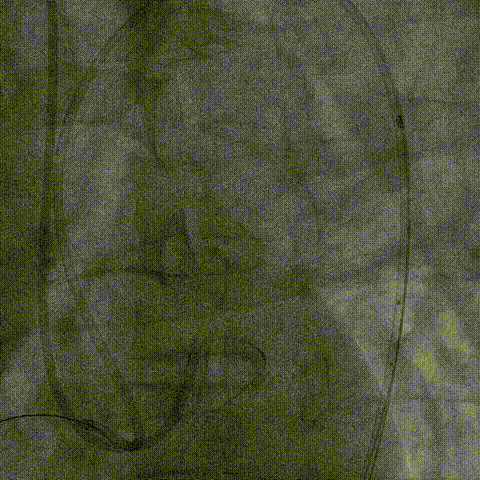

逆向器械:

1、选择近段粗大间隔支;Finecross(150cm);Sion导丝surfing通过侧枝循环至右冠远段,跟进微导管后尝试UB3、Gaia3导丝至闭塞段远段与正向导丝重叠,但闭塞段钙化可能导丝逆向导丝无法进一步前进突破。

策略转换:

1、逆向导丝无法进一步前进突破后及时转换策略,决定以逆向导丝为路标,操控正向导丝定向穿刺逆向导丝。

2、正向升级为Gaia3导丝多投照体位穿刺并靠近逆向导丝,但无法进入远端真腔,升级为Pilot200导丝试图尽量考虑血管真腔加强支撑力后启动Reverse-Cart,多体位操控后导丝幸运进入血管远端真腔。